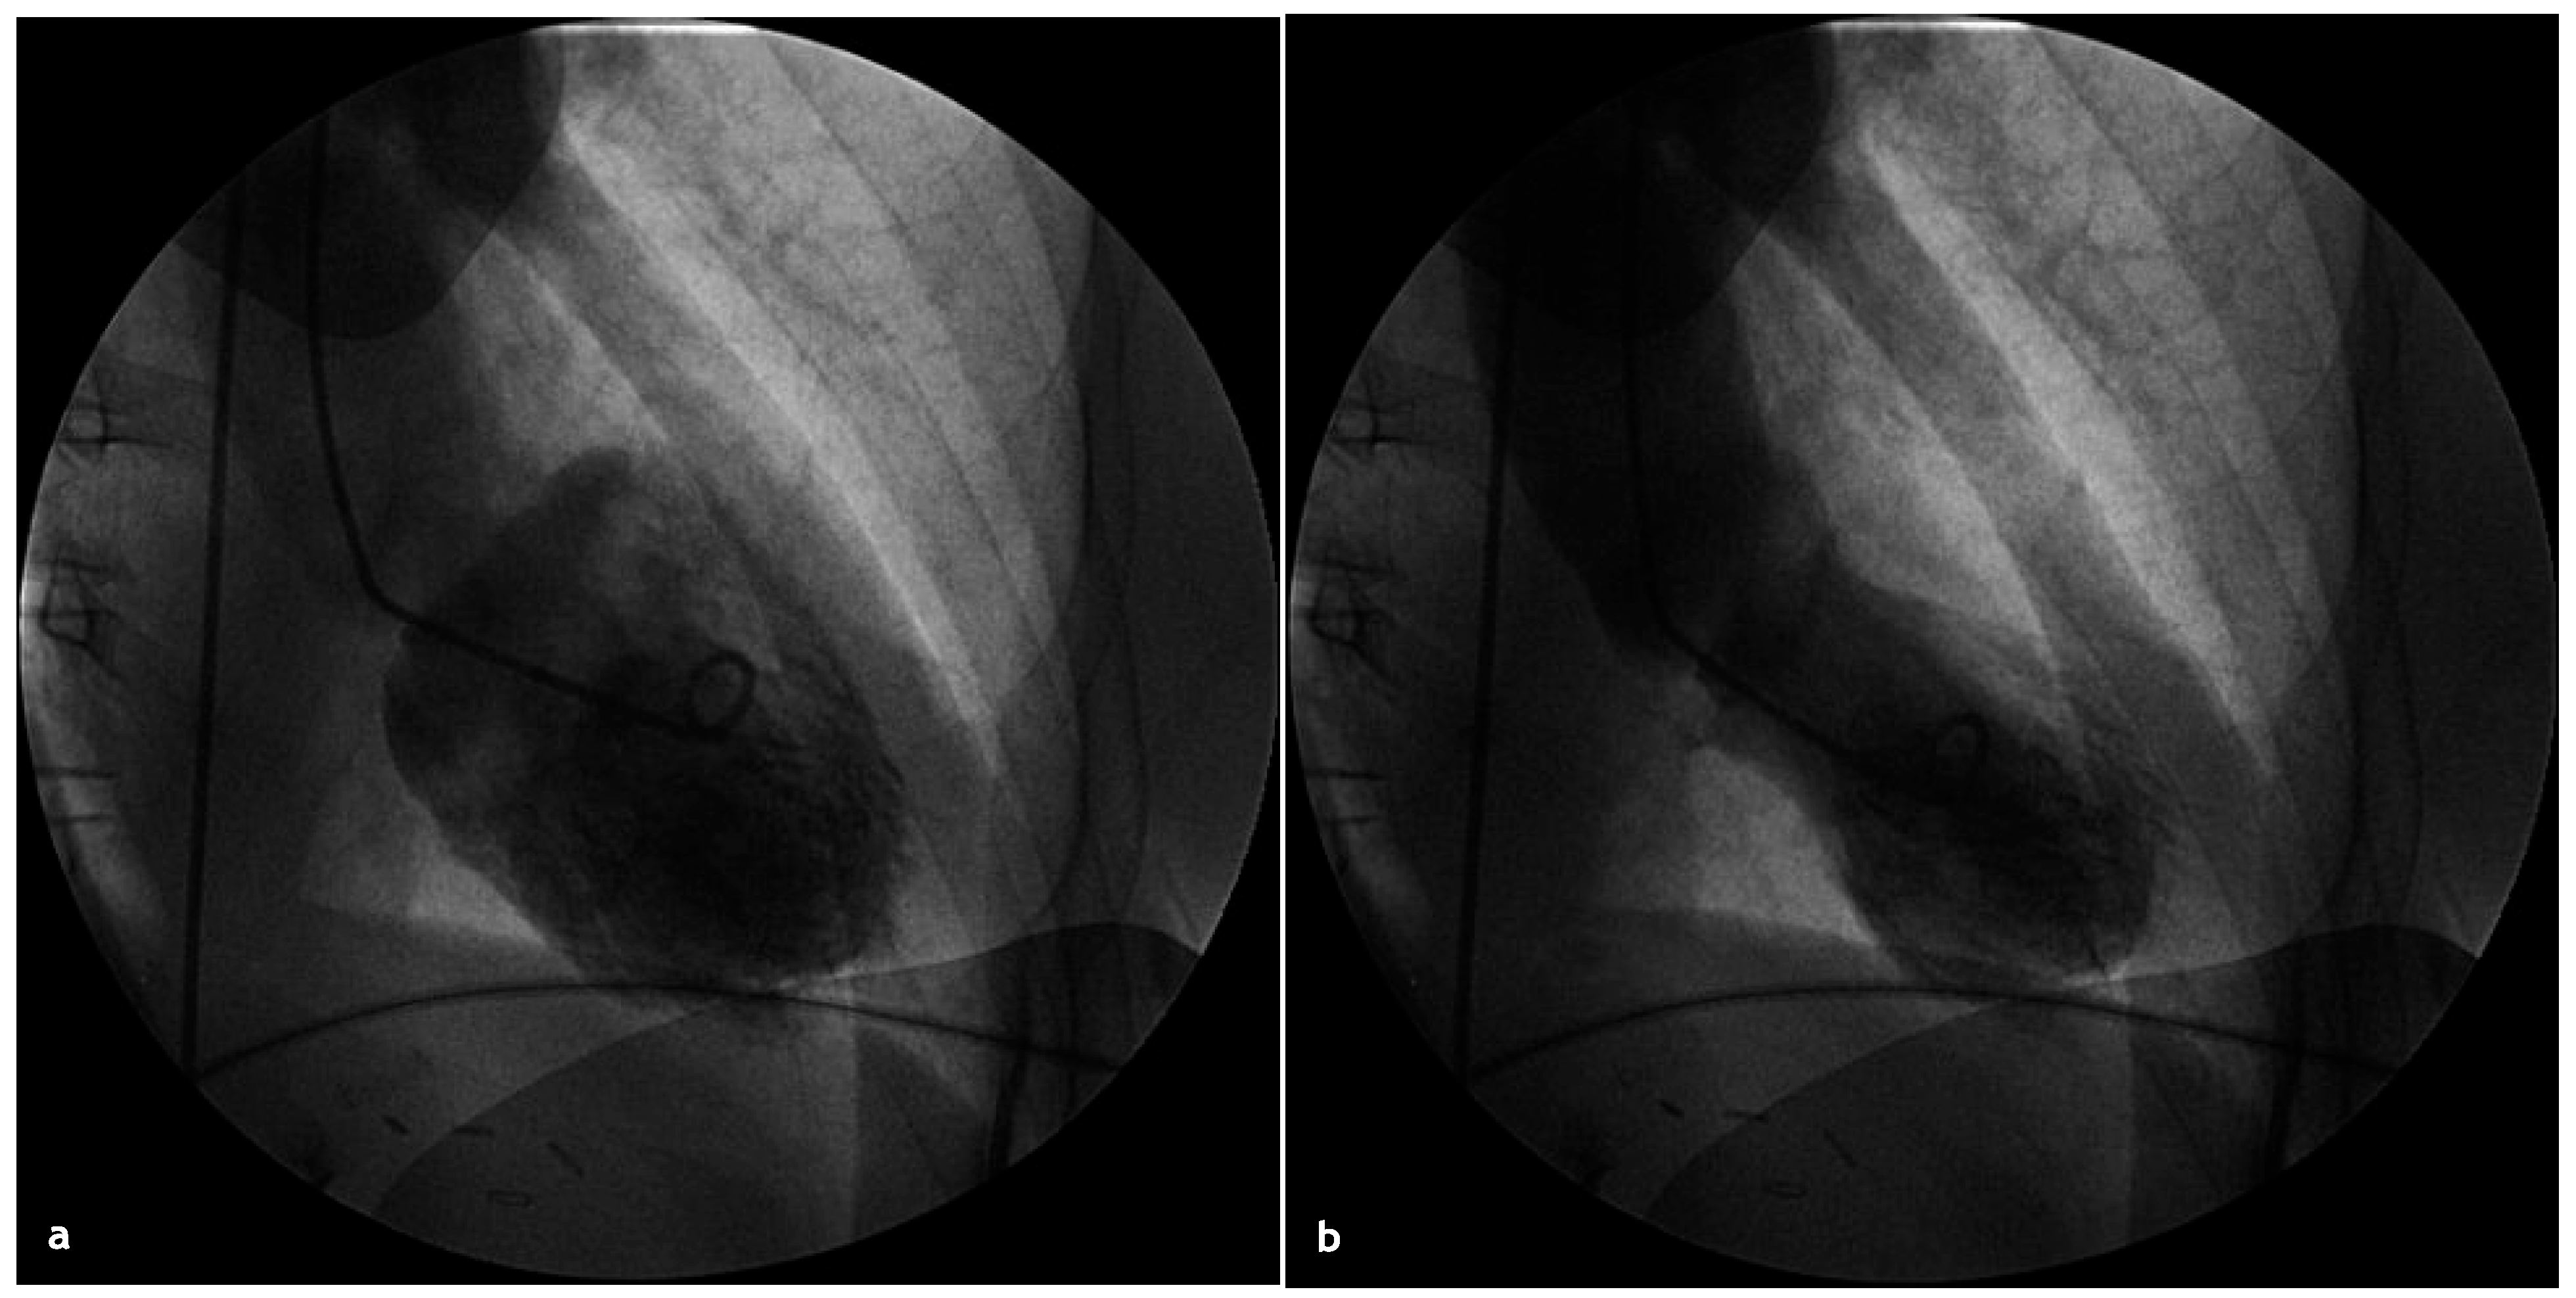

After successful CPR (patient received 3 direct current shocks, intravenous magnesium and intravenous beta-blocker before restoration of a sinus rhythm), the patient was transferred to the University Hospital for urgent angiography, which demonstrated no significant coronary artery lesions. The left ventriculography showed the typical image of an apical ballooning (Figure 4).

Figure 4. a) Left ventriculography, diastolic frame. b) Systolic frame.